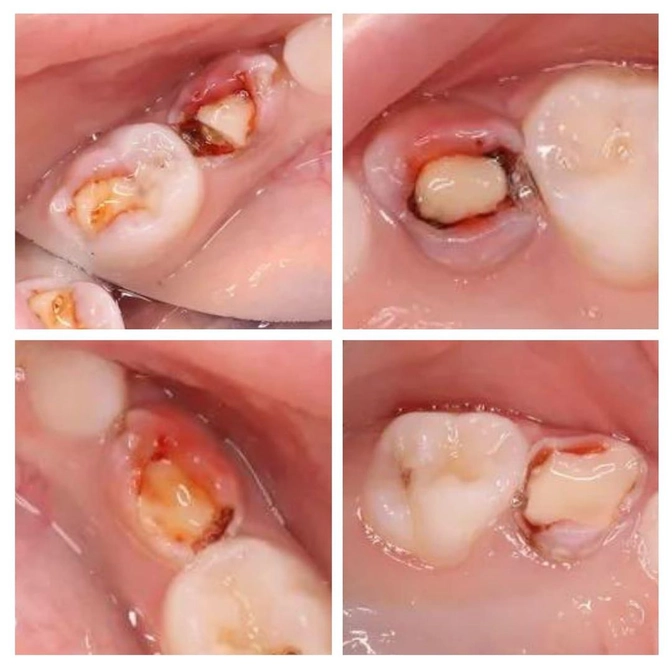

Зубы на фото взяты из нашей практики буквально на днях. Причём снято во рту ОДНОГО ребёнка.

Ребенку пролечили все молочные "четверки" и одну "пятерку" в другой клинике.

Зубы лечили буквально 3, максимум 4 месяца назад.

Сейчас они начали беспокоить ребёнка.

Использовался резорцин-формалиновый метод.

PS: практически все розовые зубы (4 из 5 зубов) пришлось удалить по показаниям.

За пятерку ещё поборемся.